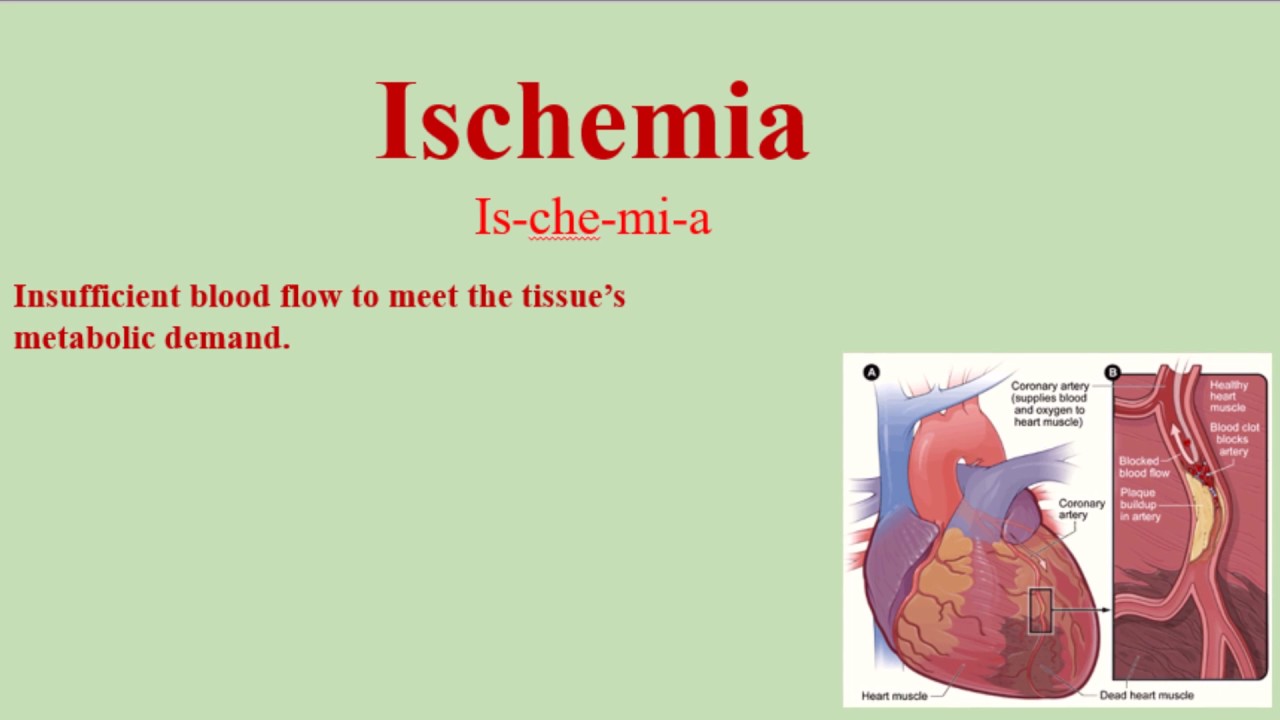

Ischemia Meaning In Medical Terms Ischemia is a serious problem where some part of your body like your heart or brain isn t getting enough blood Learn what causes it what the symptoms are and how you

Ischemia in the heart and brain often causes no symptoms and is sometimes referred to as silent ischemia and the first sign may be an unexpected heart attack or stroke When signs and Ischemia is a condition that happens when the blood supply to a part of the body is cut off Ischemia can happen to your heart limbs gastrointestinal tract and even your legs

Doctors use the term ischemia to describe a reduction in blood flow to a certain part of the body It can affect any body part including the heart brain muscle and intestines Ischemia is a significant medical condition that can lead to serious health complications if not addressed promptly Understanding its causes symptoms and treatment

Ischemia and infarction are related but distinct medical conditions Ischemia refers to the reduced blood flow to an organ or tissue which can lead to various symptoms Ischemia is defined as a decrease in blood flow below the level necessary to sustain normal cell structure and function Ischemia can be global as in cardiac arrest or severe oligemia as may